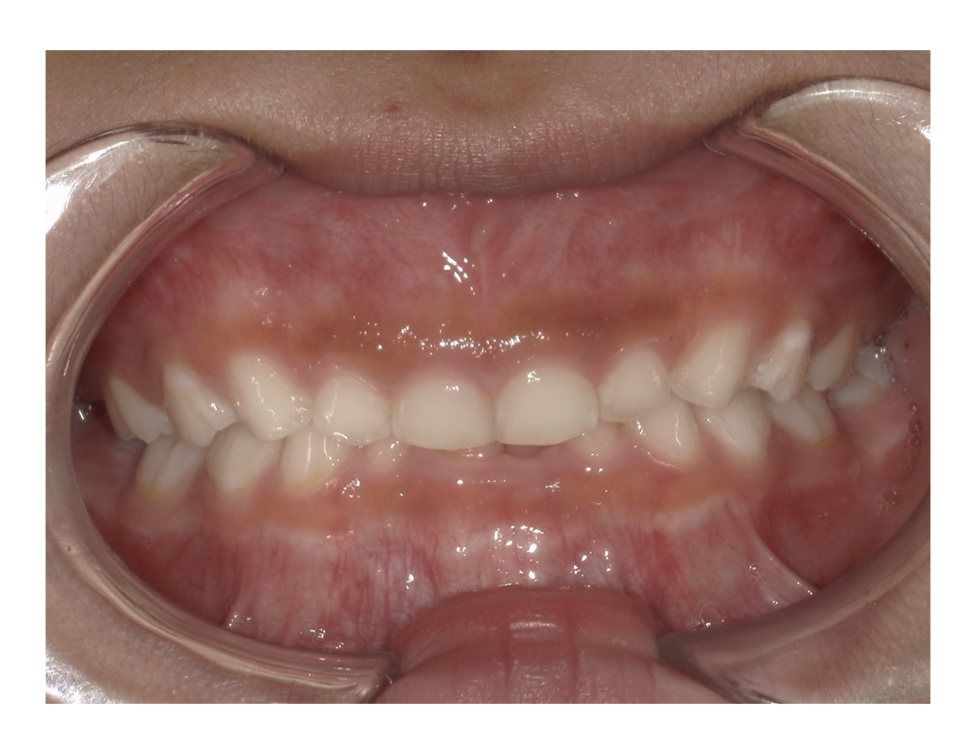

Case2

Before

After